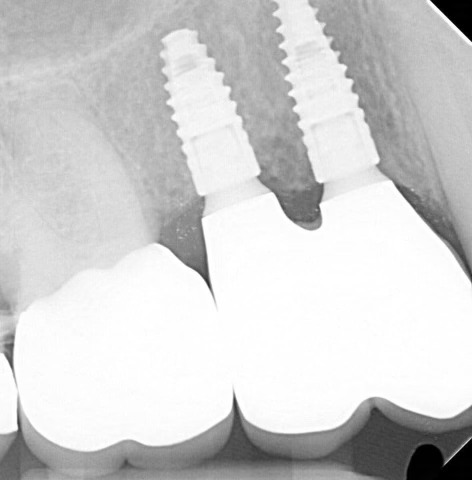

Case Study: Dental Bridges

Generate some text here.